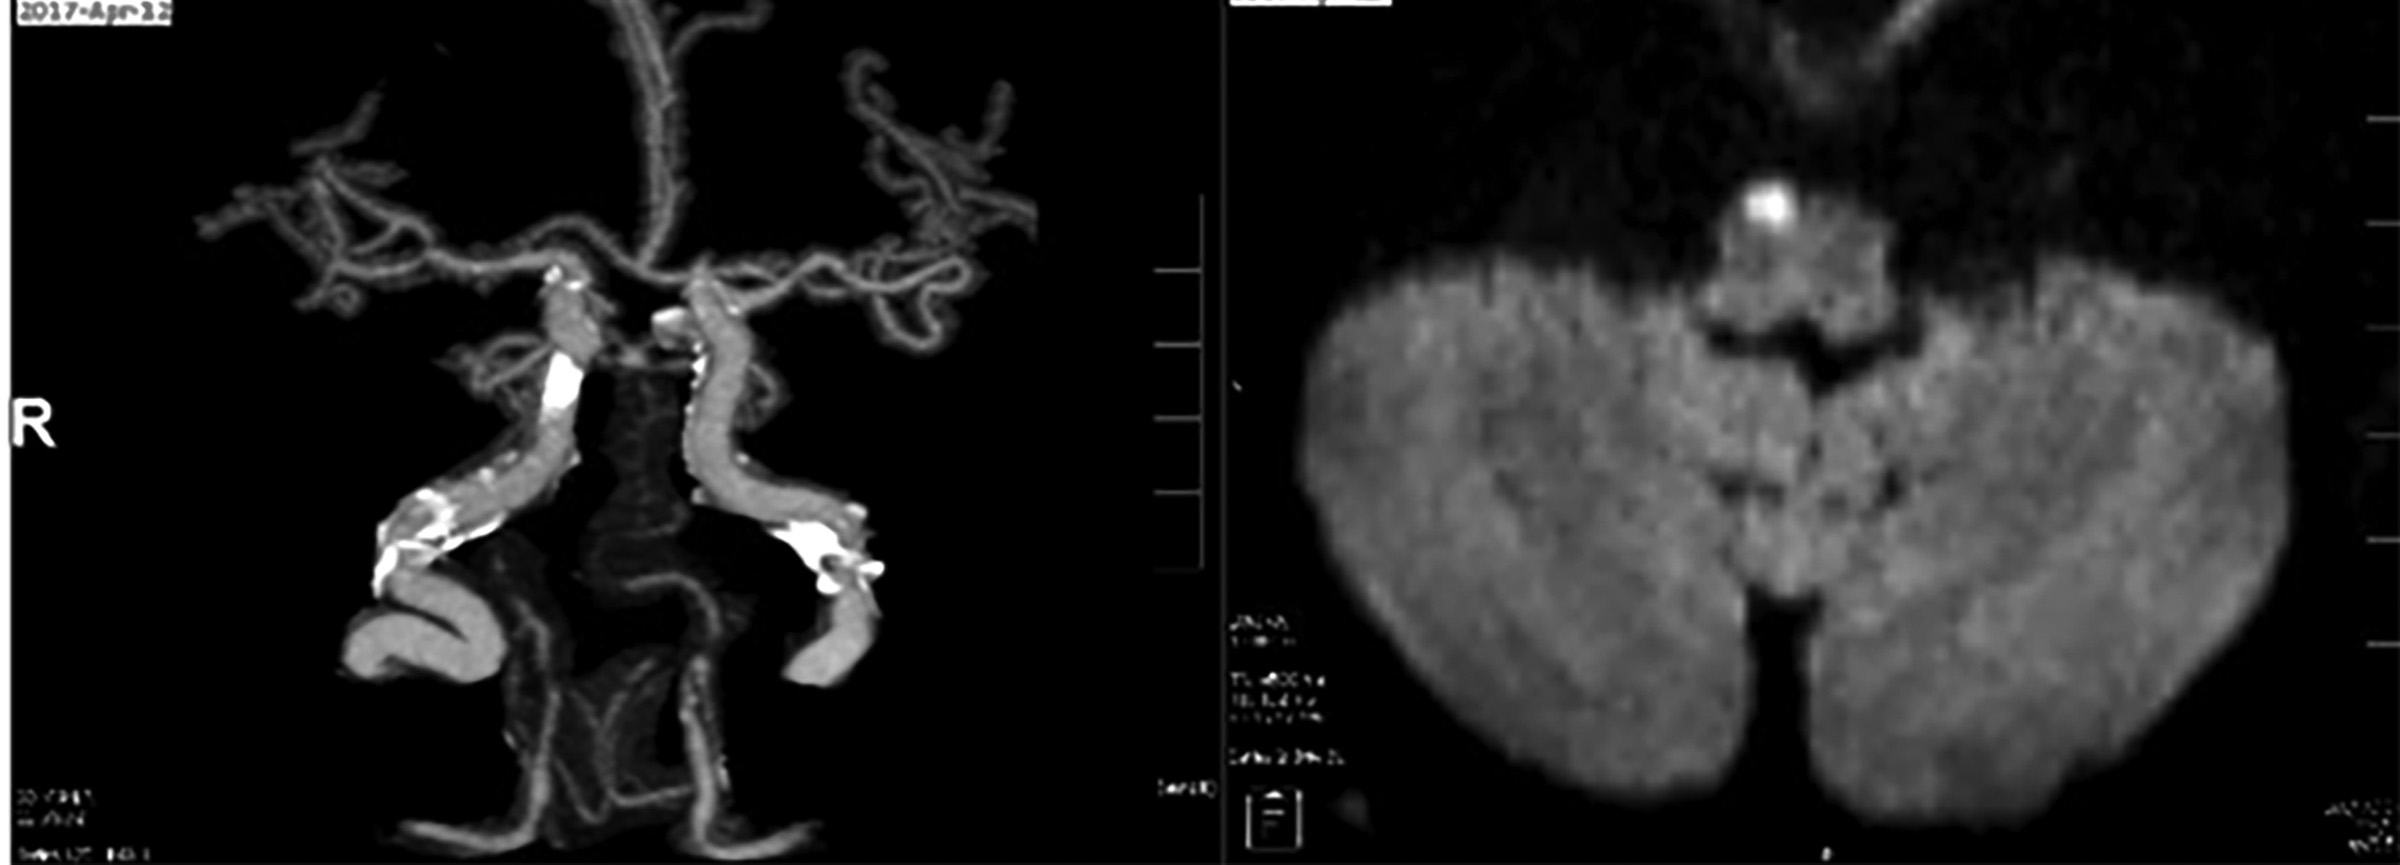

An early MRI also was falsely negative in almost 15% of patients with infarctions confirmed on delayed MRI.26 In small brainstem strokes, diffusion-weighted MRI still can miss up to 50% of the first small strokes when tested within 48 hours.23 Despite its limitations, MRI still is the diagnostic test of choice when a posterior stroke is suspected. Figure 2 shows a small acute infarct right medial ventral medulla that was not identified on CT.

Figure 2. CTA and MRI of Stroke |

![]() |

|

On the right, CT angiography shows extensive calcifications of cerebrovascular vessels. On the left, MRI demonstrates small acute infarct right medial ventral medulla. This stroke was missed on two CT scans. |